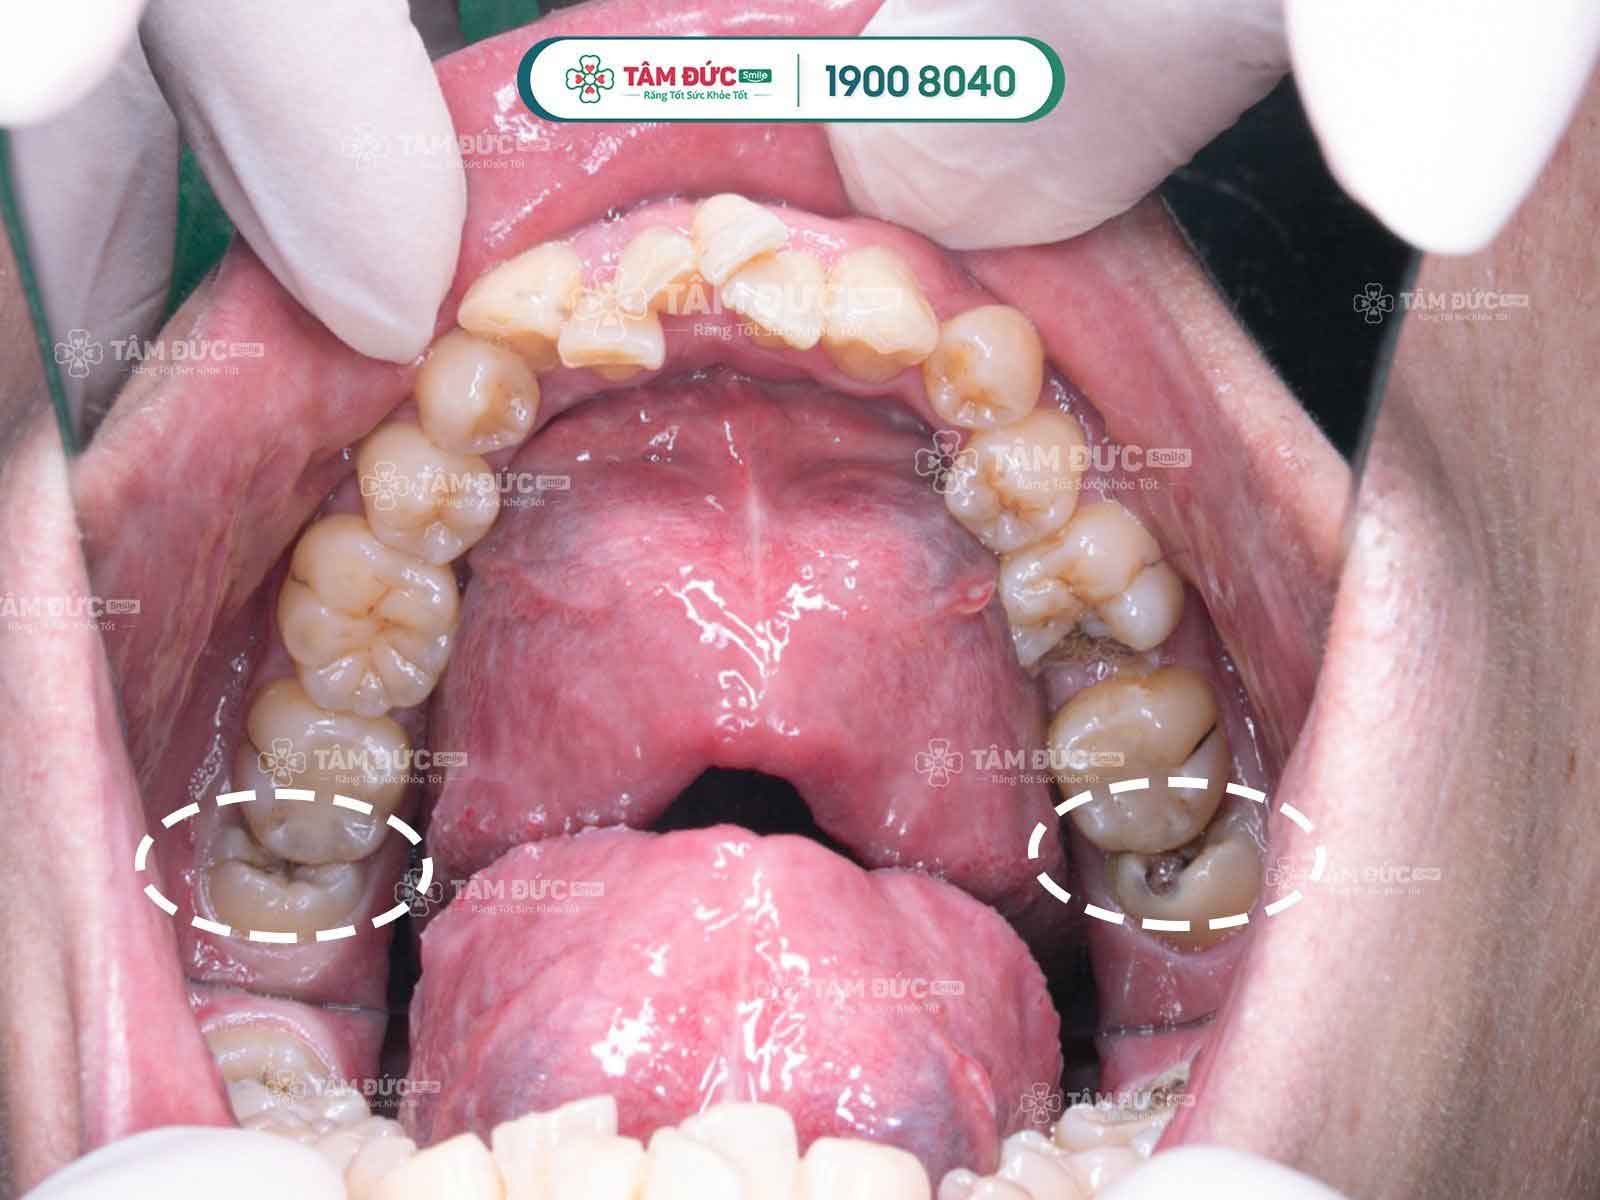

2.2. Sâu răng các răng kế bên

Giữa kẽ răng số 7 và răng khôn thường thức ăn sẽ dắt và khó làm sạch, lâu ngày sẽ làm răng số 7 bị sâu. Quý khách cần phải chú ý và quan tâm đến răng cối số 7 vì đây là răng hàm ăn nhai chính của mình.